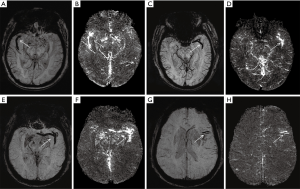

Primary SWI data with complete phase and magnitude images were processed using one button with SMARTv1.0 (susceptibility mapping and phase artifacts removal tool; Detroit, MI, USA) software within 30 s. The processing steps are detailed below. First, the unwanted low signal regions outside the brain were removed by a Brain Extraction Tool (BET) in FMRIB Software Library (FSL) (31). Second, the background phase was reduced by a 96×96 homo-dyne high-pass filter. Finally, SWIM data were generated by a truncated k-space division with a regularization threshold of 0.1 (32). The SWIM data were then observed and measured by signal processing in nuclear magnetic resonance (SPIN) (Detroit, MI, USA) software. The portions of M1 (initial and horizontal segment), M2 (Sylvian segment), and M3 (cortical segment) were marked, and susceptibility was manually measured. The detailed measurements are displayed in Figure 2A. The susceptibility of each segment was used to calculate the overall mean susceptibility of the multi-segmental thrombus. Thrombus length and CBS were measured on the SWI MinIP images along the segment of thrombus (5,33,34). The detailed measurements are shown in Figure 2B,C and Figure 3. DWI-ASPECTS was evaluated depending on the DWI and ADC images, according to the criteria of CT-ASPECTS (35,36). All of the measurements were repeated 3 times to calculate an average value by a neuroradiologist of 10-year experience and one of 5-year experience who both specialize in diseases of the central nervous system. The two readers were blinded to clinical data. The mean value of the two readers would be used if there were good consistency between them.